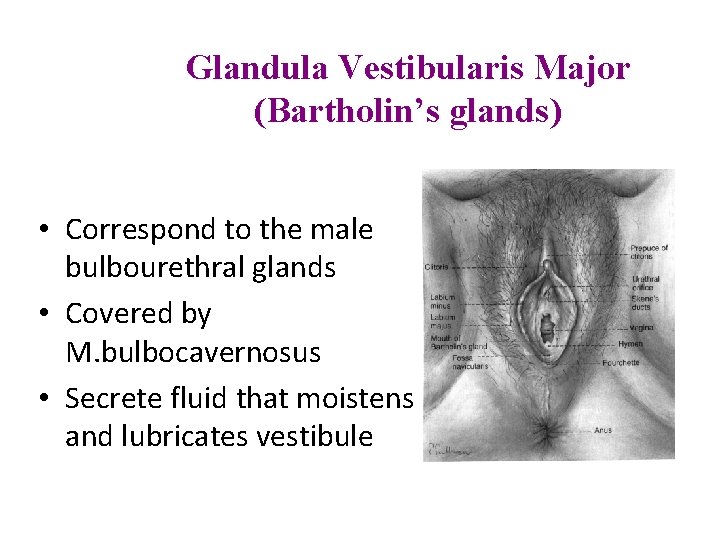

Glandula Vestibularis Major (Bartholin’s glands) • Correspond to the male bulbourethral glands • Covered by M. bulbocavernosus • Secrete fluid that moistens and lubricates vestibule